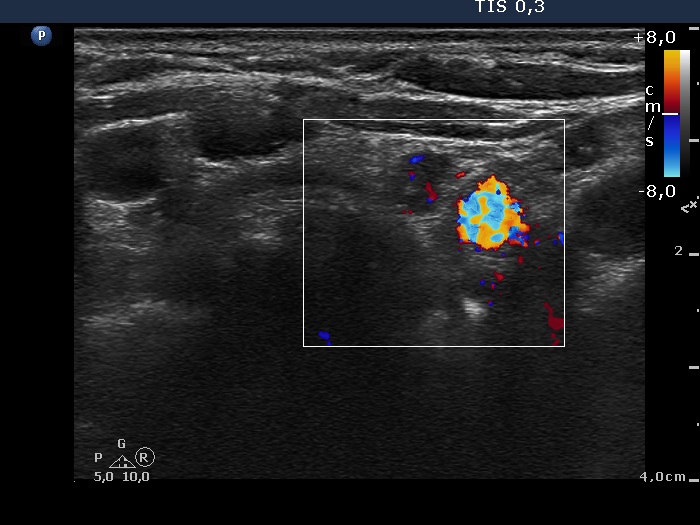

Ultrasound. Connective tissue replaced the thyroid parenchyma in both thyroid beds. There were tiny hypoechoic areas in the right thyroid bed. Two larger hypoechoic lesions were found, one in the isthmus and the other in the left thyroid bed. The latter presented vascularity.

Comment. The presentations of the hypoechoic lesion in all three sites were the same, they differed only in their size. Naturally, the two larger in the isthmus and in the left thyroid bed could cause and did cause concern. Especially that in the left lobe due to its intralesional vascularity. The larger lesions can correspond to small muscle fibers, remnant of the regenerative provess after the surgery but even damaged, non-viable thyroid tissue. Taking the thyroglobulin level into account, the risk of thyroid cancer is minimal but not zero.